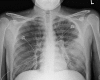

Case report: A young woman with history of asthma presented with complaints of nausea, vomiting, abdominal pain, wheezing, and dry cough. Physical examination revealed diffuse expiratory wheezing and mild diffuse abdominal pain without rebound or guarding. Laboratory results showed leukocytosis with eosinophilia. Stool studies showed Strongyloides stercoralis. Imaging revealed ground-glass opacities in the right upper and lower lobe along with an infiltrate in the lingular lobe on the left side. Bronchoscopy showed Strongyloides stercoralis. The patient was diagnosed with hyperinfection syndrome due to Strongyloides stercoralis most probably exacerbated by prednisone given for her asthma. Steroids were then discontinued and the patient was started on ivermectin. The patient improved with treatment. Repeat stool examination was negative for Strongyloides stercoralis.